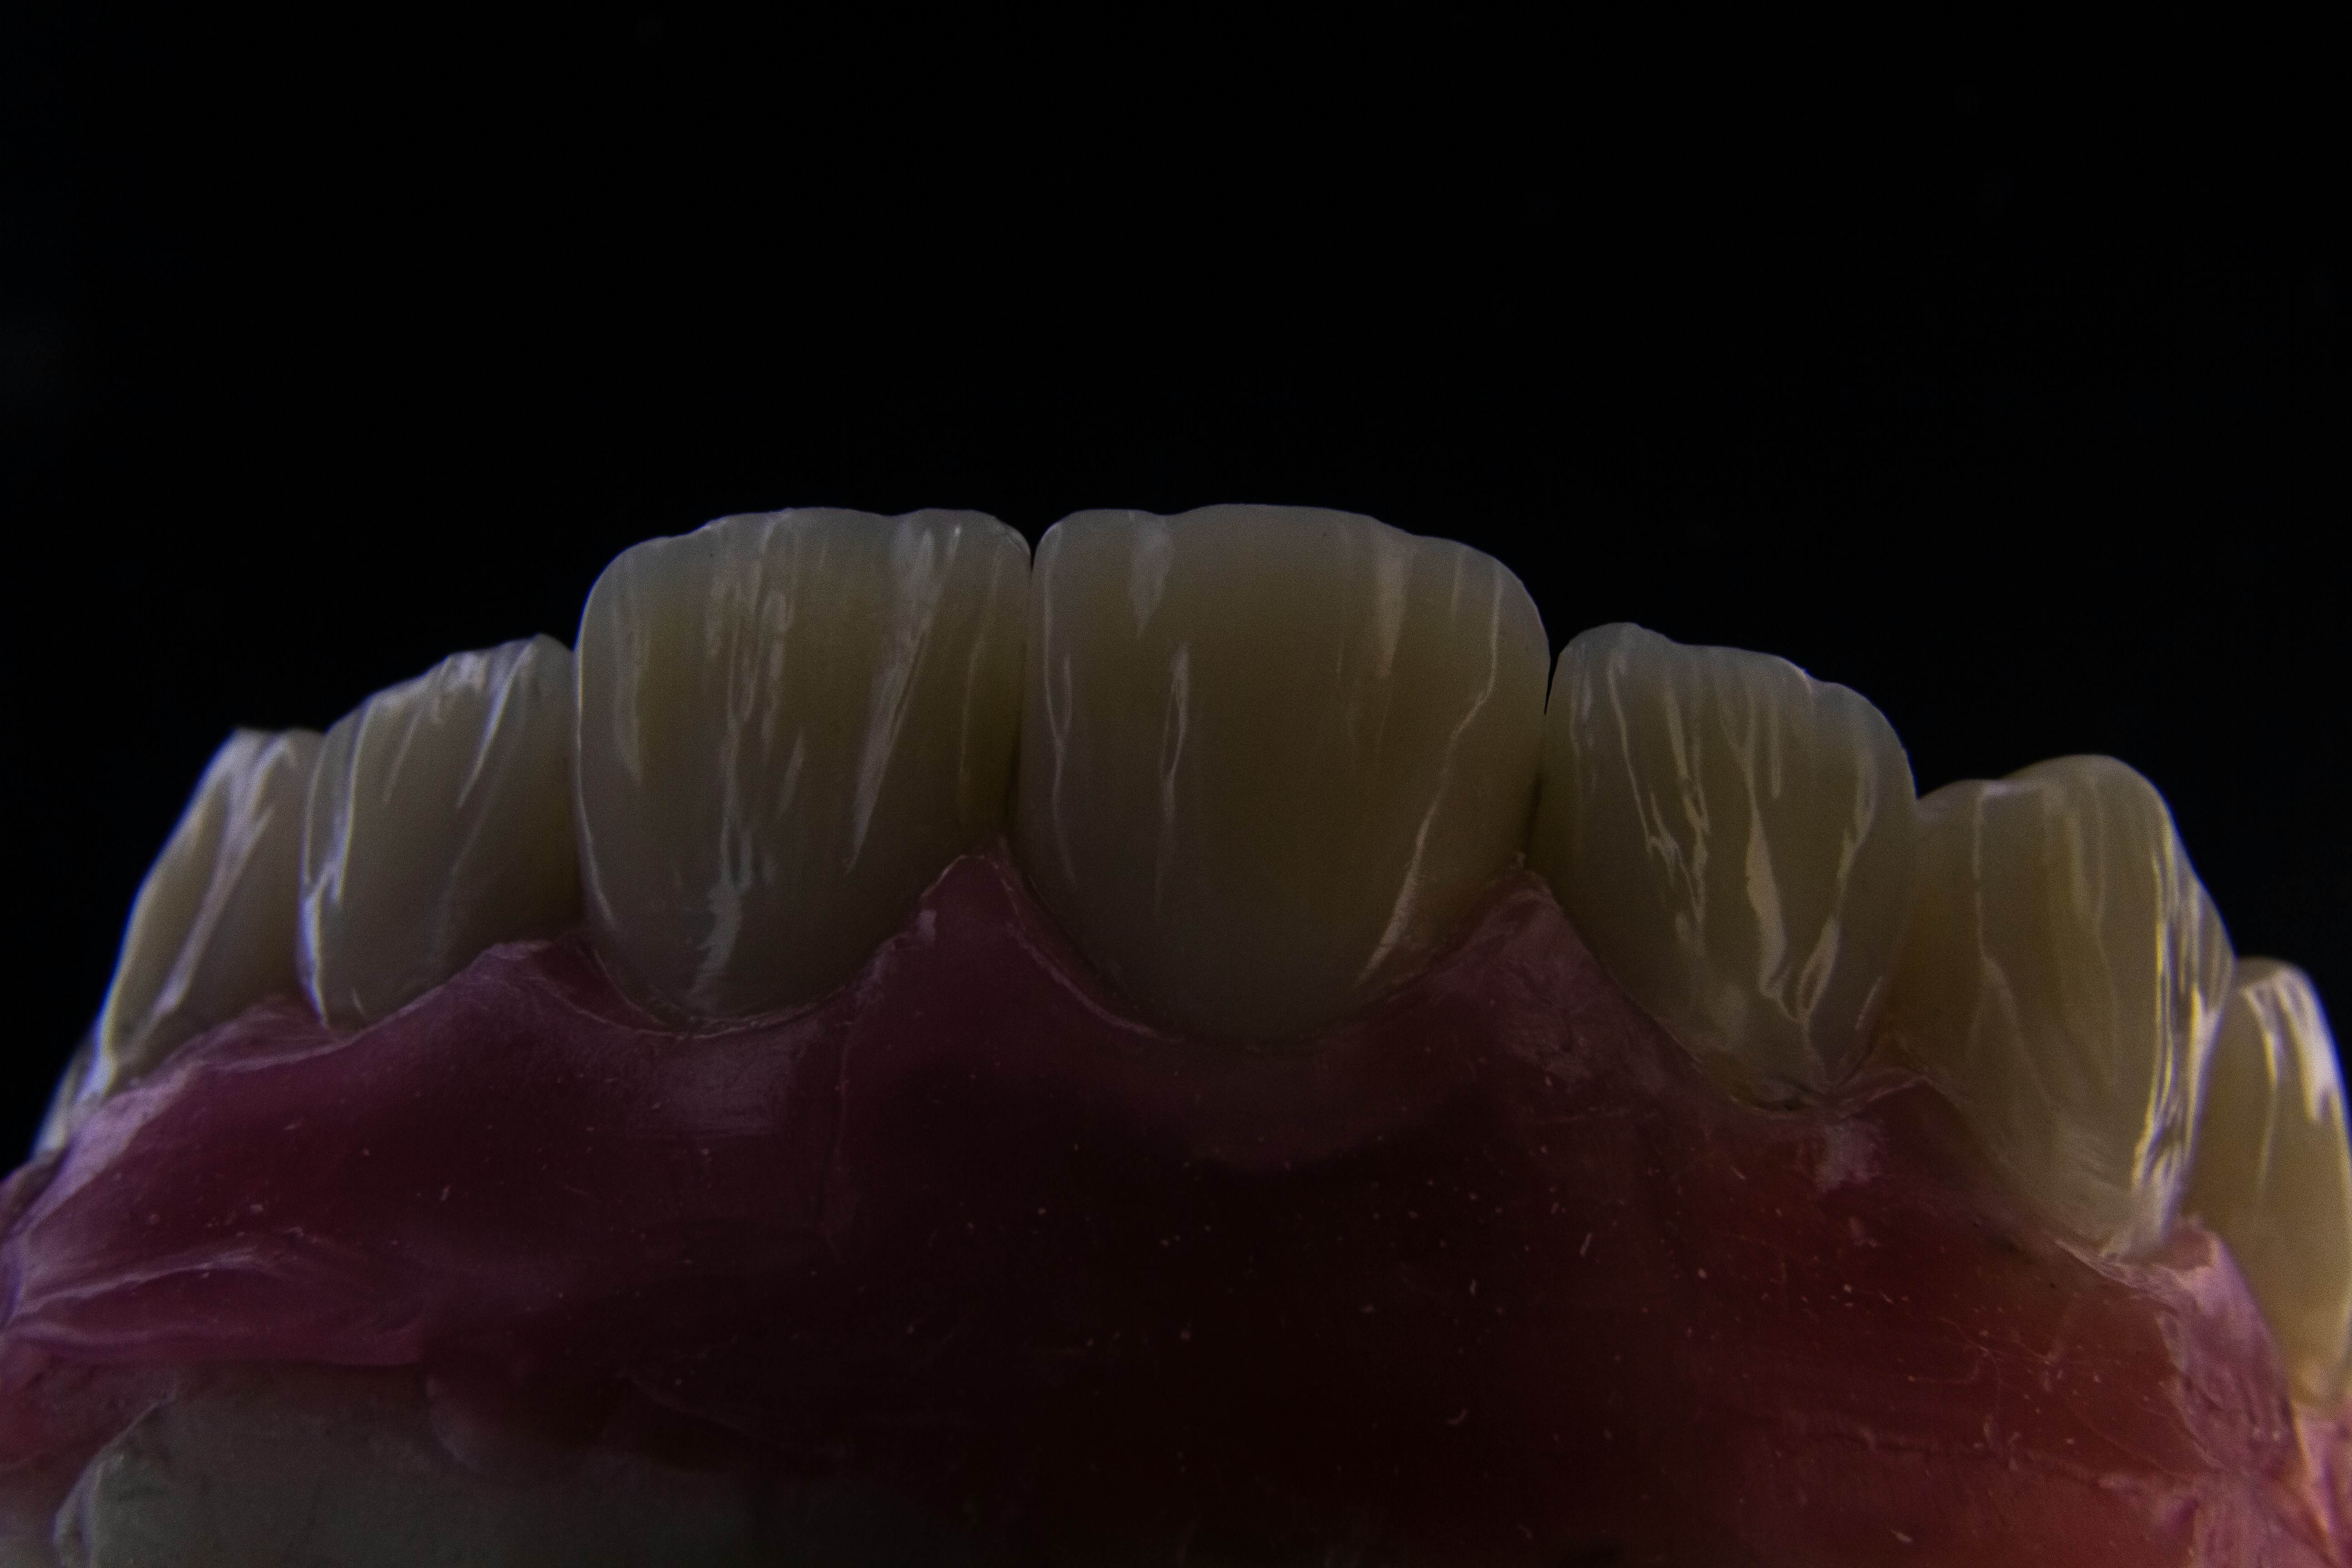

How Albanian dental labs produce high-quality crowns, veneers, and prosthetics using advanced CAD/CAM technology.

A Hollywood Smile makeover is one of the most searched cosmetic dental treatments. Learn how clinics in Albania approach planning, veneers, crowns, and smile design.